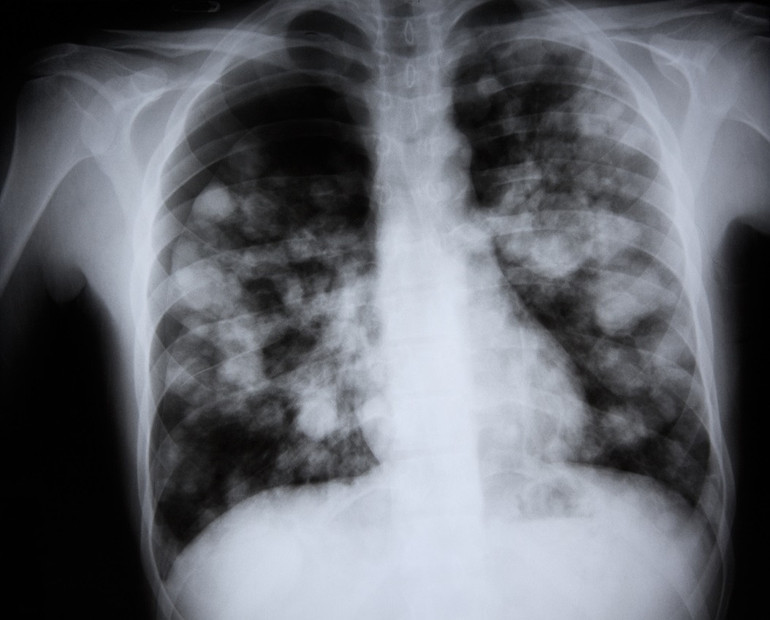

Zatürre, akciğerlerde iltihaplanmaya yol açan ciddi bir enfeksiyon hastalığı. Özellikle çocuklar ve yaşlılar için tehlikeli olabilen bu hastalık, gribal enfeksiyon gibi daha basit bir rahatsızlık sonrası gelişebiliyor. Bu durumu yaşayanlardan biri de Bursa’da yaşayan Turgay ve Fatma Gazioğlu’nun 5 yaşındaki oğulları Erdal Gazioğlu oldu.

Orhangazi Devlet Hastanesi’nde yaklaşık 20 gün tedavi gören ve daha önce Bursa Şehir Hastanesine sevk edilen beş yaşındaki Erdal Gazioğlu, burada zatürre tanısı ile yaklaşık bir hafta tedavi gördükten sonra fenalaşarak hayatını kaybetti. Minik Erdal’ın ölümü ailesi ve yakınlarını yasa boğarken, yaşanan bu olay zatürrenin tehlikeli bir hastalık olduğunu bir kez daha gözler önüne serdi.

Prof. Dr. Muhammed Emin Akkoyunlu, “Aslında bir haftada sonuç alınabileceği doğru. Fakat şunu söylemek lazım ki, bazen enfeksiyonun ötesine geçerek çeşitli organ yetmezliklerine veya dokuların etkilenmesine neden olabiliyor. Akciğerlerde direnç kazanarak farklı sorunlara yol açabilen bu durum, tedavi sürecini karmaşık hale getirebilir. Bu nedenle, zatürrenin sadece antibiyotikle değil, hayatta kalmayı sağlamak için diğer destek tedavilerle de ele alınması önemli” dedi.

Son olayda yaşanan bir aylık sürecin sadece spesifik bir zatürre tedavisi olmayabileceğine de dikkat çeken Prof. Dr. Akkoyunlu, “Eğer enfeksiyon direnç kazanmışsa veya savunma sisteminin zayıflamasına bağlı bir tablo ortaya çıkmışsa, tedavi süreci çok daha uzun sürebilir. Özellikle savunma sistemi zayıf olan ve uzun süre yoğun bakımda kalan hastalarda, zatürre tedavileri oldukça uzayabiliyor. Bu durum, tedavi sürecinin karmaşıklığını da artırıyor” şeklinde konuştu.

Üst solunum enfeksiyonlarının halk arasında bazen de yanlışlıkla doktorlar arasında zatürre olarak tanımlanmamasının zatürrenin hafife alınmasına neden olduğunu vurgulayan Prof. Dr. Muhammed Emin Akkoyunlu, “Her yıl dünya genelinde yaklaşık 450 milyon kişi zatürre oluyor ve bu sayı sürekli artıyor. Bu da dünya nüfusunun neredeyse yaklaşık yüzde 7’sine denk geliyor. Bu hastalık her yıl milyonlarca insanın hayatını kaybetmesine neden oluyor. Dolayısıyla, zatürre ciddi ve hayatı tehdit eden bir hastalık” dedi.